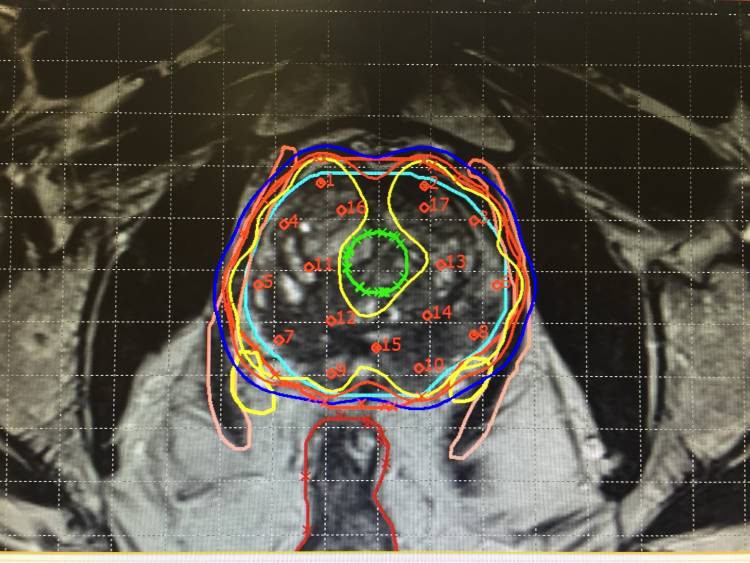

(圖片:A. Vargas/國際原子能機構)放療涉及使用精心選擇的電離輻射劑量來破壞癌細胞的 DNA。DNA 控制著它們如何分裂。輻射會導致腫瘤縮小,在某些情況下會導致腫瘤死亡。自 1890 年代以來,放射療法已被用于治療幾乎所有類型的癌癥。它可以單獨使用或與其他治療方法(例如化學療法或手術)結合使用,以治愈癌癥或控制疾病的癥狀。

成像用于制定治療計劃:從藥物治療和放射治療到手術,或者在某些情況下用于姑息治療。在放射治療計劃期間,醫學成像會生成腫瘤的三維圖像,從而可以更好地針對腫瘤進行放射治療,同時最大限度地減少對健康組織的損害。

圖像引導放射治療 (IGRT) 將實時醫學成像納入放射治療過程,以確保準確和一致地提供輻射劑量。

詳細的醫學圖像使衛生專業人員能夠區分腫瘤、健康組織和器官,以確保癌細胞被正確定位。(照片:Auna Oncosalud)原子能機構的作用是什么?